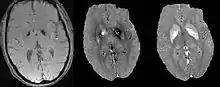

Differentiating calcification from iron

It has been confirmed in in vivo and phantom experiments that cortical bones, whose major composition is calcification, are diamagnetic compared to water.[11][18] Therefore, it is possible to use this diamagnetism to differentiate calcifications from iron deposits that usually demonstrate strong paramagnetism.[19] This may allow QSM to serve as a problem solving tool for the diagnosis of confounding hypointense findings on T2* weighted images.

Quantification of contrast agent

For exogenous susceptibility sources, the susceptibility value is theoretically linearly proportional to the concentration of the contrast agent. This provides a new way for in vivo quantification of gadolinium or SPIO concentrations.[20]